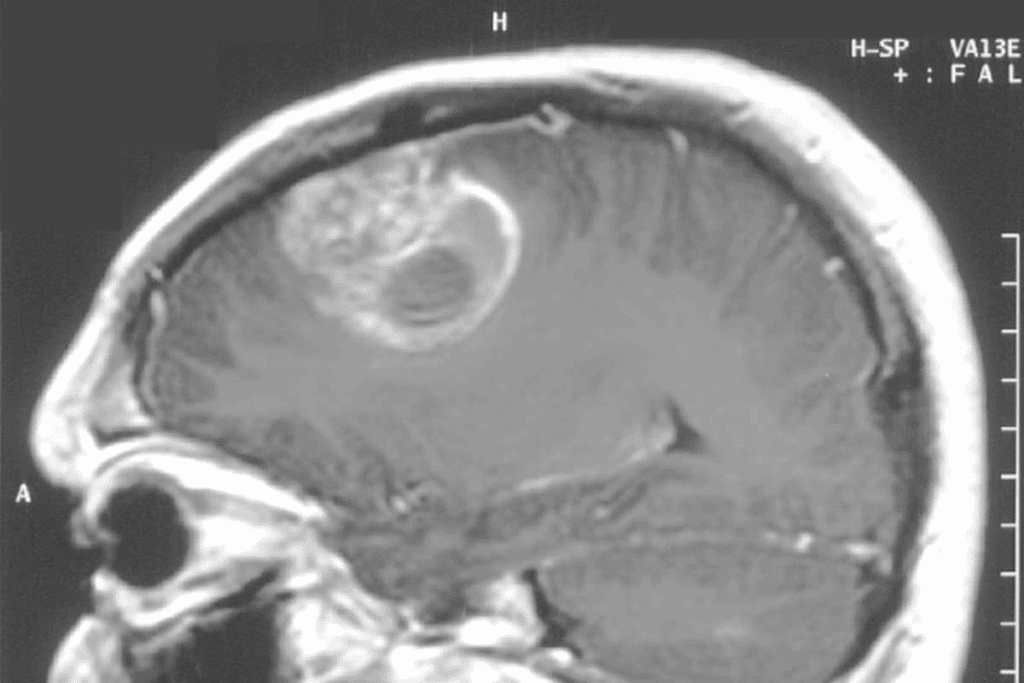

Imaging Studies (MRI, CT Scan)

Imaging tests are key in diagnosing brain tumors. We use Magnetic Resonance Imaging (MRI) and Computed Tomography (CT) scans to see the tumor’s details. MRI is best for soft tissue and is often used for brain tumors.

The benefits of MRI include:

- High-resolution images of soft tissues

- Ability to detect tumors in various brain regions

- Detailed information for surgical planning